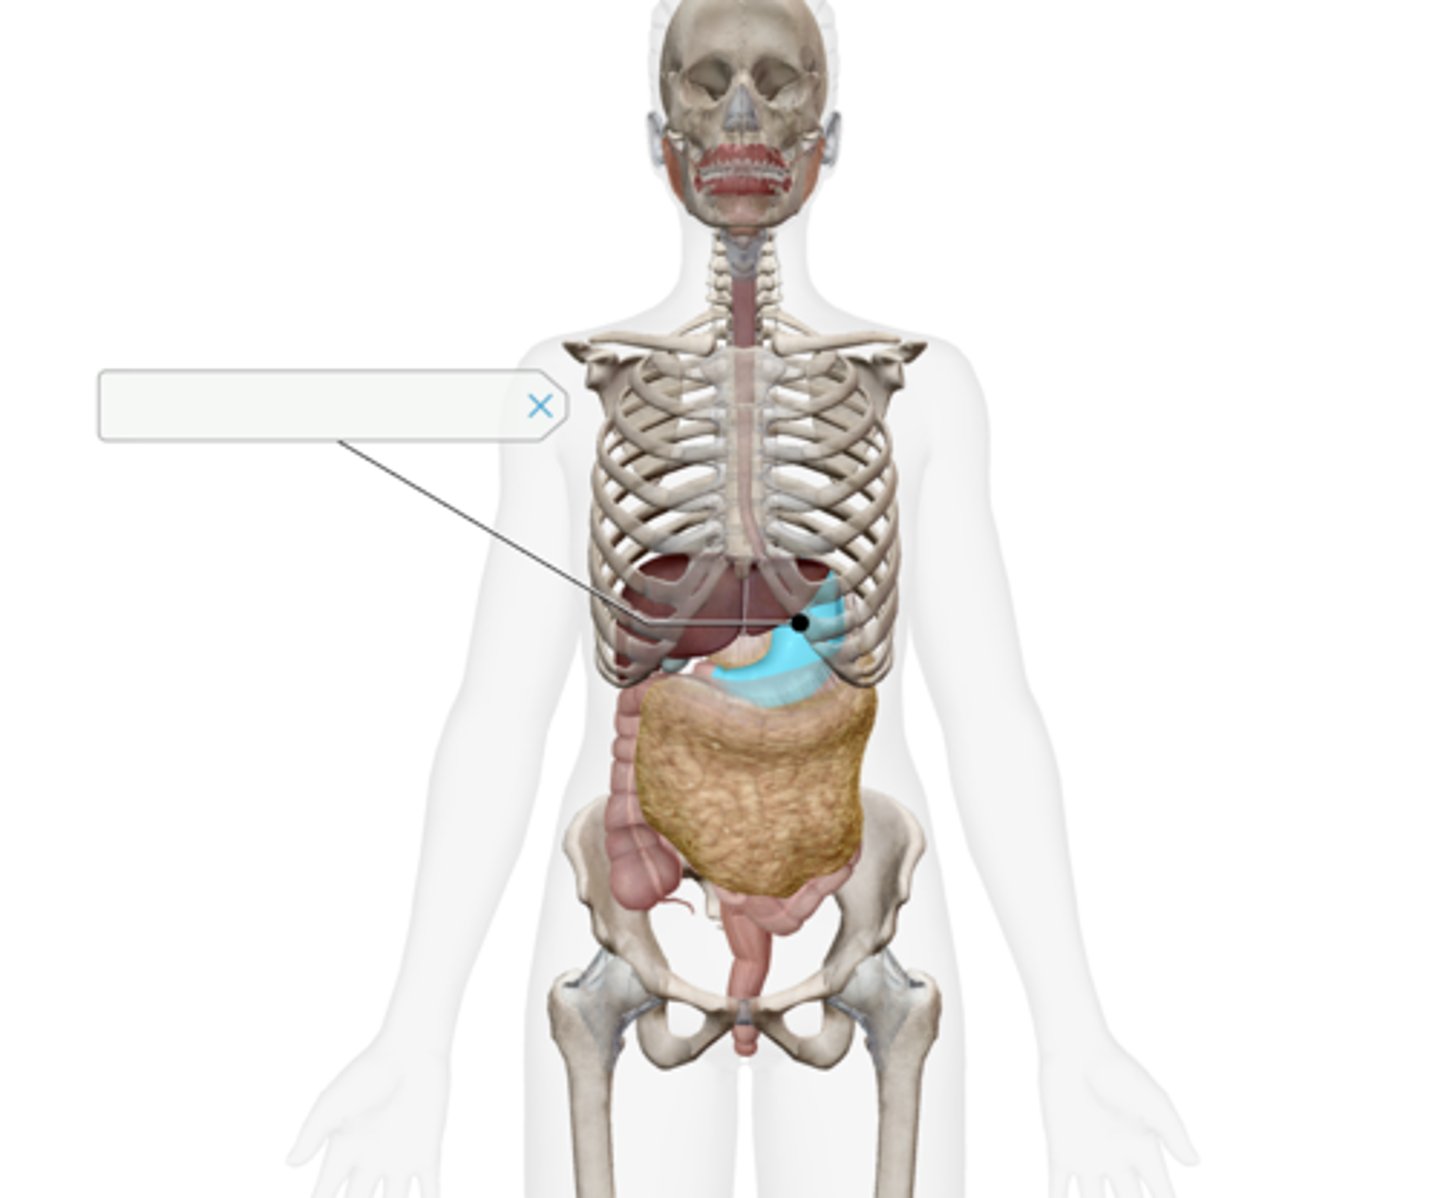

Gallbladder

Pancreas

Liver